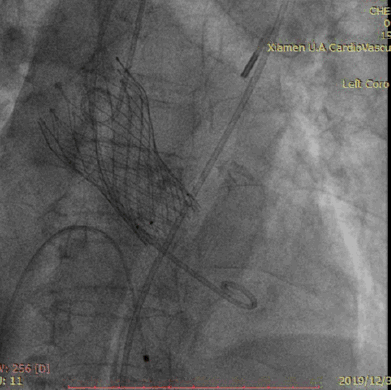

释放VenusA-Valve L26瓣膜

瓣膜释放后造影